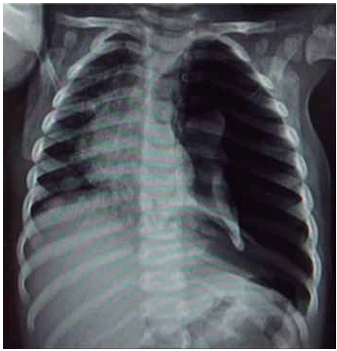

Lactente de 6 meses com tosse, coriza e desconforto respiratório progressivo há 2 dias (chega a ficar “roxinho” nos lábios quando mama, segundo a mãe). Nega internações ou problemas de saúde prévios. Foi trazido ao pronto-socorro devido a piora do desconforto, palidez cutânea e inapetência, com importante comprometimento do estado geral. Ao exame físico, está em mau estado geral, descorado +++/4+, extremidades frias, tempo de enchimento capilar de 5 segundos, pulsos finos, FC = 200 bpm, PA = 62 x 33 (43) mmHg, SatO2 = 87% em ar ambiente, FR = 68 ipm, ausculta pulmonar com estertores crepitantes em bases e ausculta cardíaca com bulhas rítmicas normofonéticas com sopro sistólico +/6+ em borda esternal esquerda. Obtido ritmo cardíaco e radiografia de tórax a seguir.

Enunciado 4584195-1

(Arquivo pessoal; imagens usadas com autorização)

Com base nos dados apresentados, assinale a alternativa que contenha a hipótese diagnóstica mais provável e a conduta mais adequada para o caso.